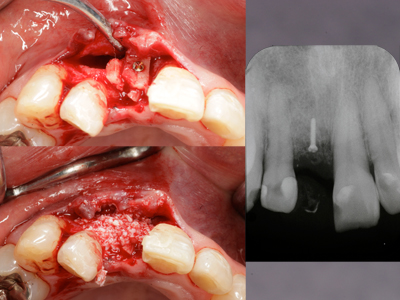

GBRの歯科インプラントへの応用。骨造成を併用したインプラント症例 - 相模原市矢部の歯医者。さかもと歯科医院】GBR、人工骨について | さかもと歯科医院。インプラントのご相談は、博多の「加茂歯科医院」へ。